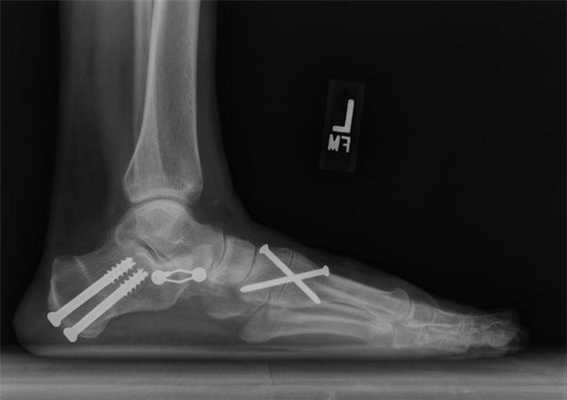

Медиализирующая остеотомия пяточной кости в сочетании с таранно-ладъевидным артродезом.

Не так давно ученые провели исследование и выяснили, какие методики наиболее эффективны в лечении продольного плоскостопия. Лучшим методом коррекции оказалась медиализирующая остеотомия пяточной кости в сочетании с таранно-ладъевидным артродезом. Она дает хороший клинический результат и редко приводит к осложнениям. В отличие от подтаранного артродеза, после такого лечения больному не требуется повторное хирургическое вмешательство.

Операция продольно-поперечной деформации.

При поперечно-продольном плоскостопии человеку делают сразу несколько вмешательств. Например, больному одновременно выполняют операцию Шеде, остеотомию Scarf и артродезирование некоторых суставов плюсны. Как правило, врачи стараются сделать все за одно хирургическое вмешательство.